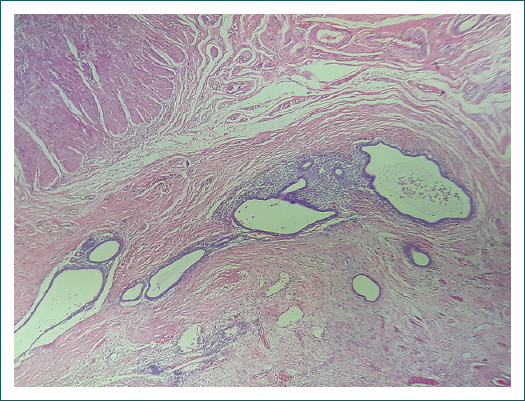

Por persistencia del dolor abdominal intenso y ante la evidencia clínica de obstrucción intestinal, es revalorada por el servicio de cirugía general y se le realiza laparotomía exploradora, con hallazgo de un tumor a nivel del íleon terminal y la válvula ileocecal de 3 × 4 cm, condicionando estenosis a dicho nivel, dilatación de íleon distal, ganglios mesentéricos ahulados e implantes de apariencia endometriósica en los últimos 100 cm de intestino delgado, ameritando resección intestinal con hemicolectomía derecha e ileostomía terminal. Se envía la muestra obtenida a patología, que reporta endometriosis activa intestinal intramural, subserosa y en tejido adiposo pericolónico con hiperplasia de tejido linfoide (Figs. 3 y 4).

Los cambios histopatológicos generados son en un inicio inflamatorios, con fase reparativa y fibrosa en su etapa terminal.13 De acuerdo con los estudios publicados, existe una estrecha relación entre el grado de endometriosis y la afección perineural o endoneural. Las características patognomónicas de este tipo de lesión son el epitelio endometrial y glándulas o estroma del endometrio con o sin presencia de hemorragia, siendo este el caso en nuestra paciente. Se encuentra relacionada la aparición de carcinomas endometrioides, y raramente la transformación sarcomatosa.9, 13